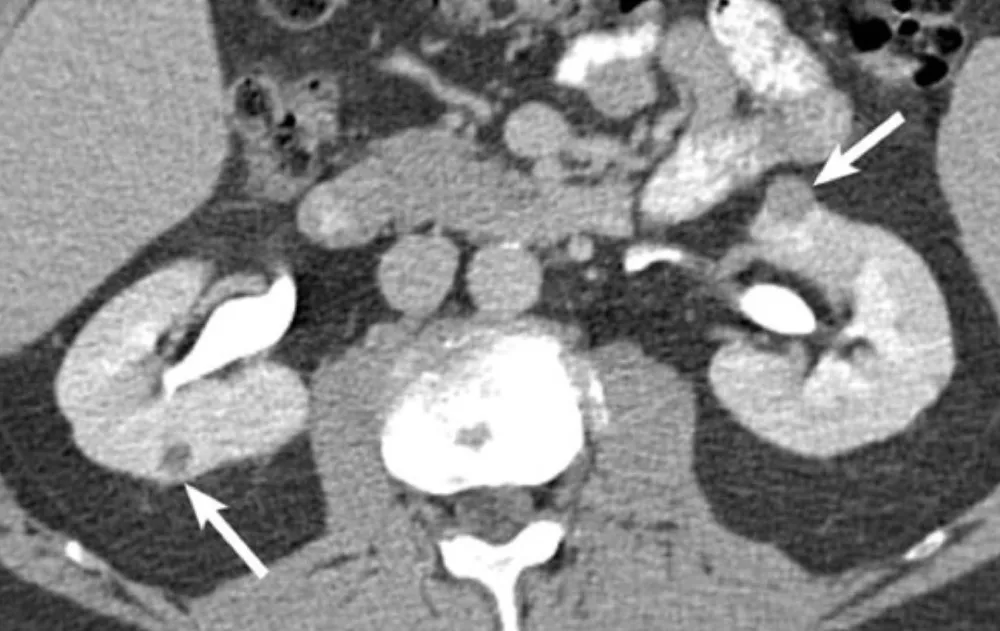

Uma causa incomum de hematúria glomerular intermitente!

Uma causa incomum de hematúria glomerular intermitente!

Hematúria pós infecção, caso clínicos para auxiliar no entendimento de causas glomerulares comuns e raras...